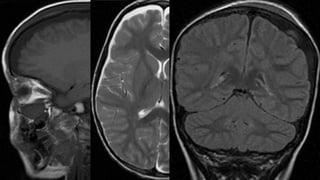

Este documento presenta el caso de un niño de 3 años que sufrió episodios de paresia y alteraciones neurológicas. Exámenes revelaron la presencia de un higroma cerebral que fue drenado. A pesar de una mejoría inicial, el niño continuó presentando síntomas neurológicos intermitentes. Exámenes posteriores identificaron una rara vasculopatía que afecta vasos cerebrales y otros órganos, con un pronóstico grave.